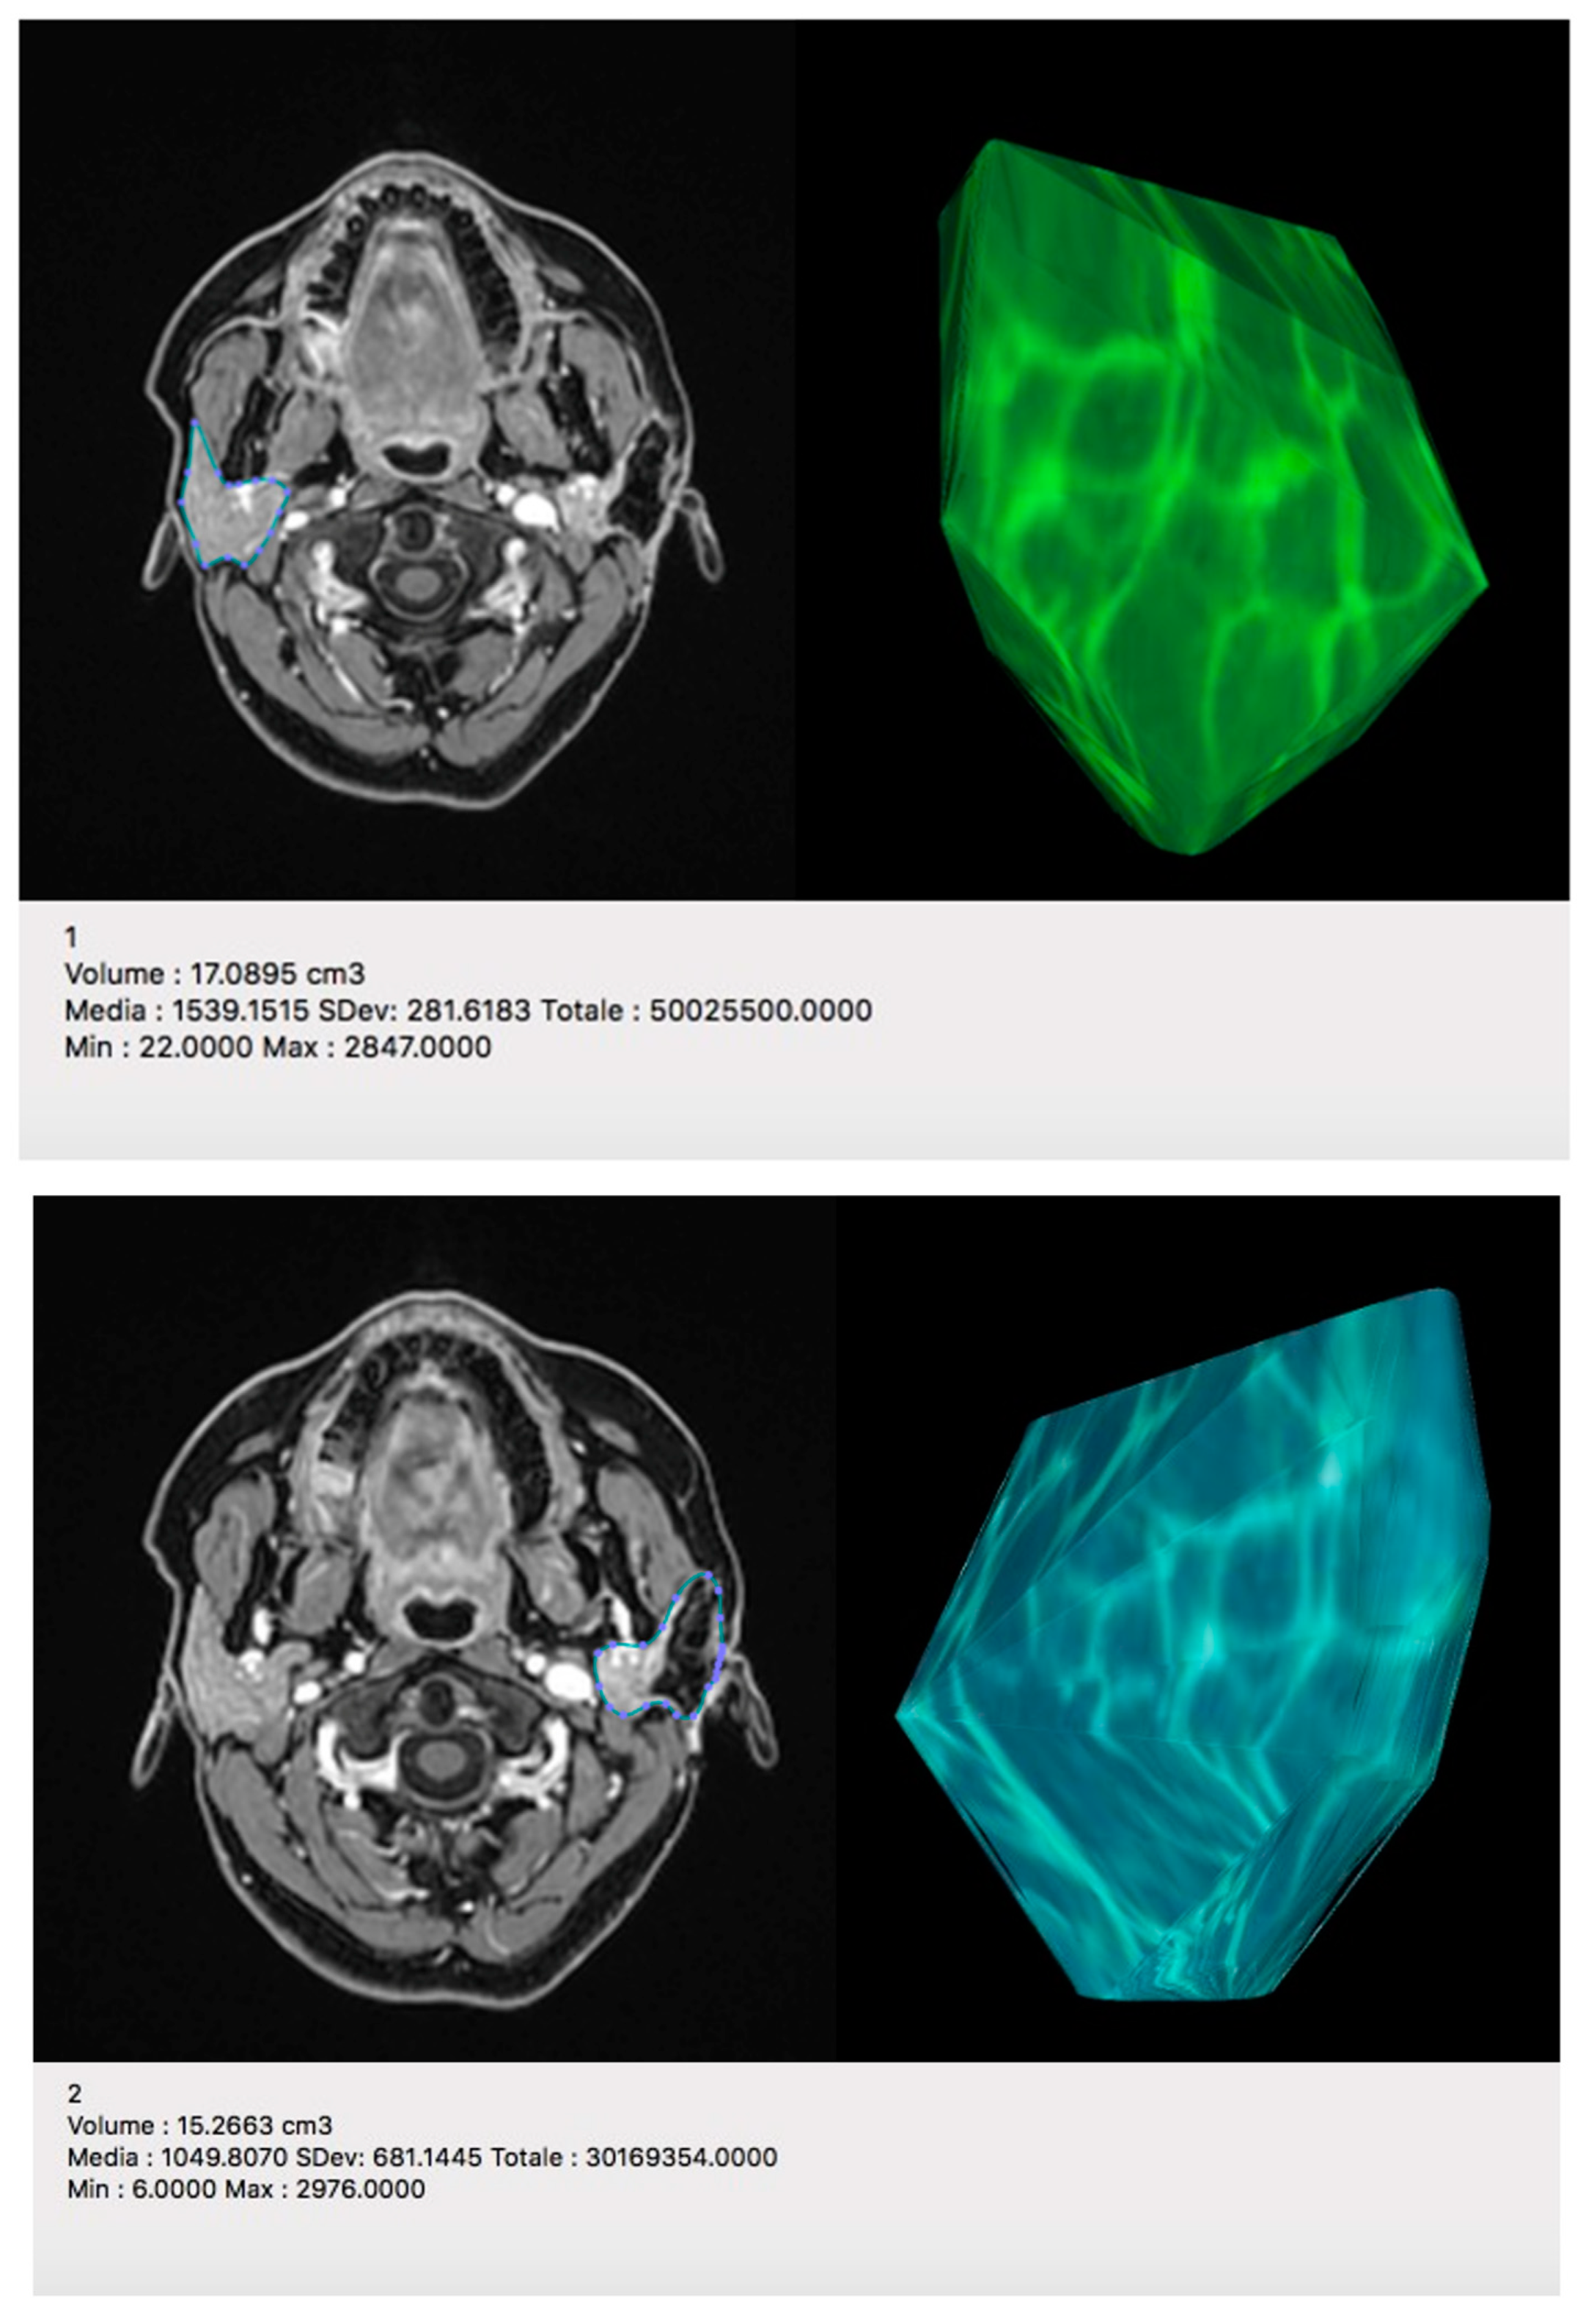

4.1.1. MRI Protocol

4.1.2. MRI Analysis